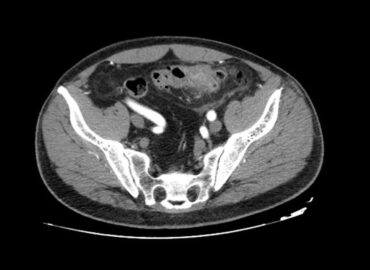

Paciente femenina de 51 años, DBT tipo II. Dolor colico hemiabdomen inferior izquierdo